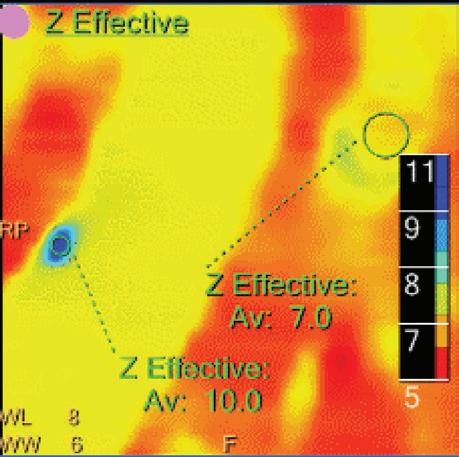

Z Effective (Zeff)

Effective atomic number. Each voxel is set to a value in the range 5 to 30 representing the effective atomic number of that voxel. Z effective of air is set to zero. For reference, Z effective of water is 7.4, Z effective of cortical bone is 13.2, and Z effective of fat is 5.9. Z effective maps are very sensitive to materials characteristics (Figure 3) and can also be used to display perfusion maps and to identify very subtle perfusion deficits (Figure 2b). The accuracy measured on a Gammex phantom with iodine, calcium, and soft tissue inserts show that the majority of Z effective values are within 0.2 Z effective units and are consistent between 120 and 140 kVp scans.21

Double oblique MPR image shows a calcified lesion and a uric acid stone side by side. The lower row displays spectral results in the Magic Glass, from left to right: conventional CT image, uric acid removed image, uric acid image, and Z effective map image. A comparative measurement on the conventional image shows that it is not possible to differentiate between them based on HU measurements (Calcified: 326.2 HU; UA stone: 329.4 HU). The Z effective map shows a large difference between the lesions (Calcified: 10.0; UA stone: 7.0) which enables us to classify them correctly.